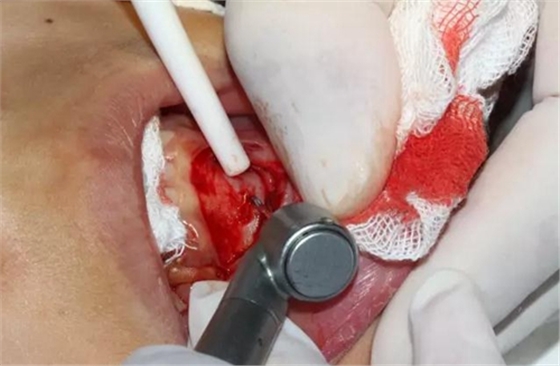

口腔局部浸潤(rùn)麻醉,手術(shù)鋪巾

切開(kāi)、翻瓣

去除骨皮質(zhì),暴露牙冠大部分